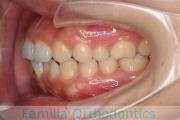

No.22V-299

- 上顎前突

- 叢生

- 30歳

- 女性

- 上:

- 44

- 下:

- 主な使用装置:

- FEA 022

- 治療にかかった費用:

- 90万円

上の出っ歯、口が閉じにくい、下の前歯のガタガタを治したいということで来院されました。上顎から左右小臼歯を、下の前歯は凹凸が非常に強いので、こちらから一本抜歯を行いました。2年強、30回程度の通院が必要でした。

成人になってからの叢生(でこぼこ、凹凸、ガタガタ)は、保定をしっかりしないと後戻りをしてしまうリスクが高いです。